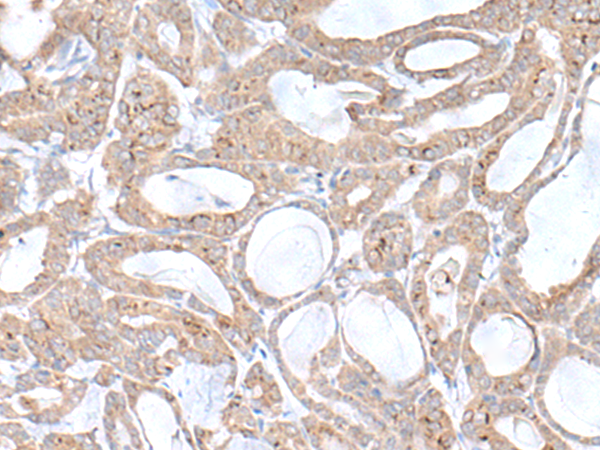

分类: 科研抗体货号: P09809别名: PLGP1应用: IHC反应种属: Human